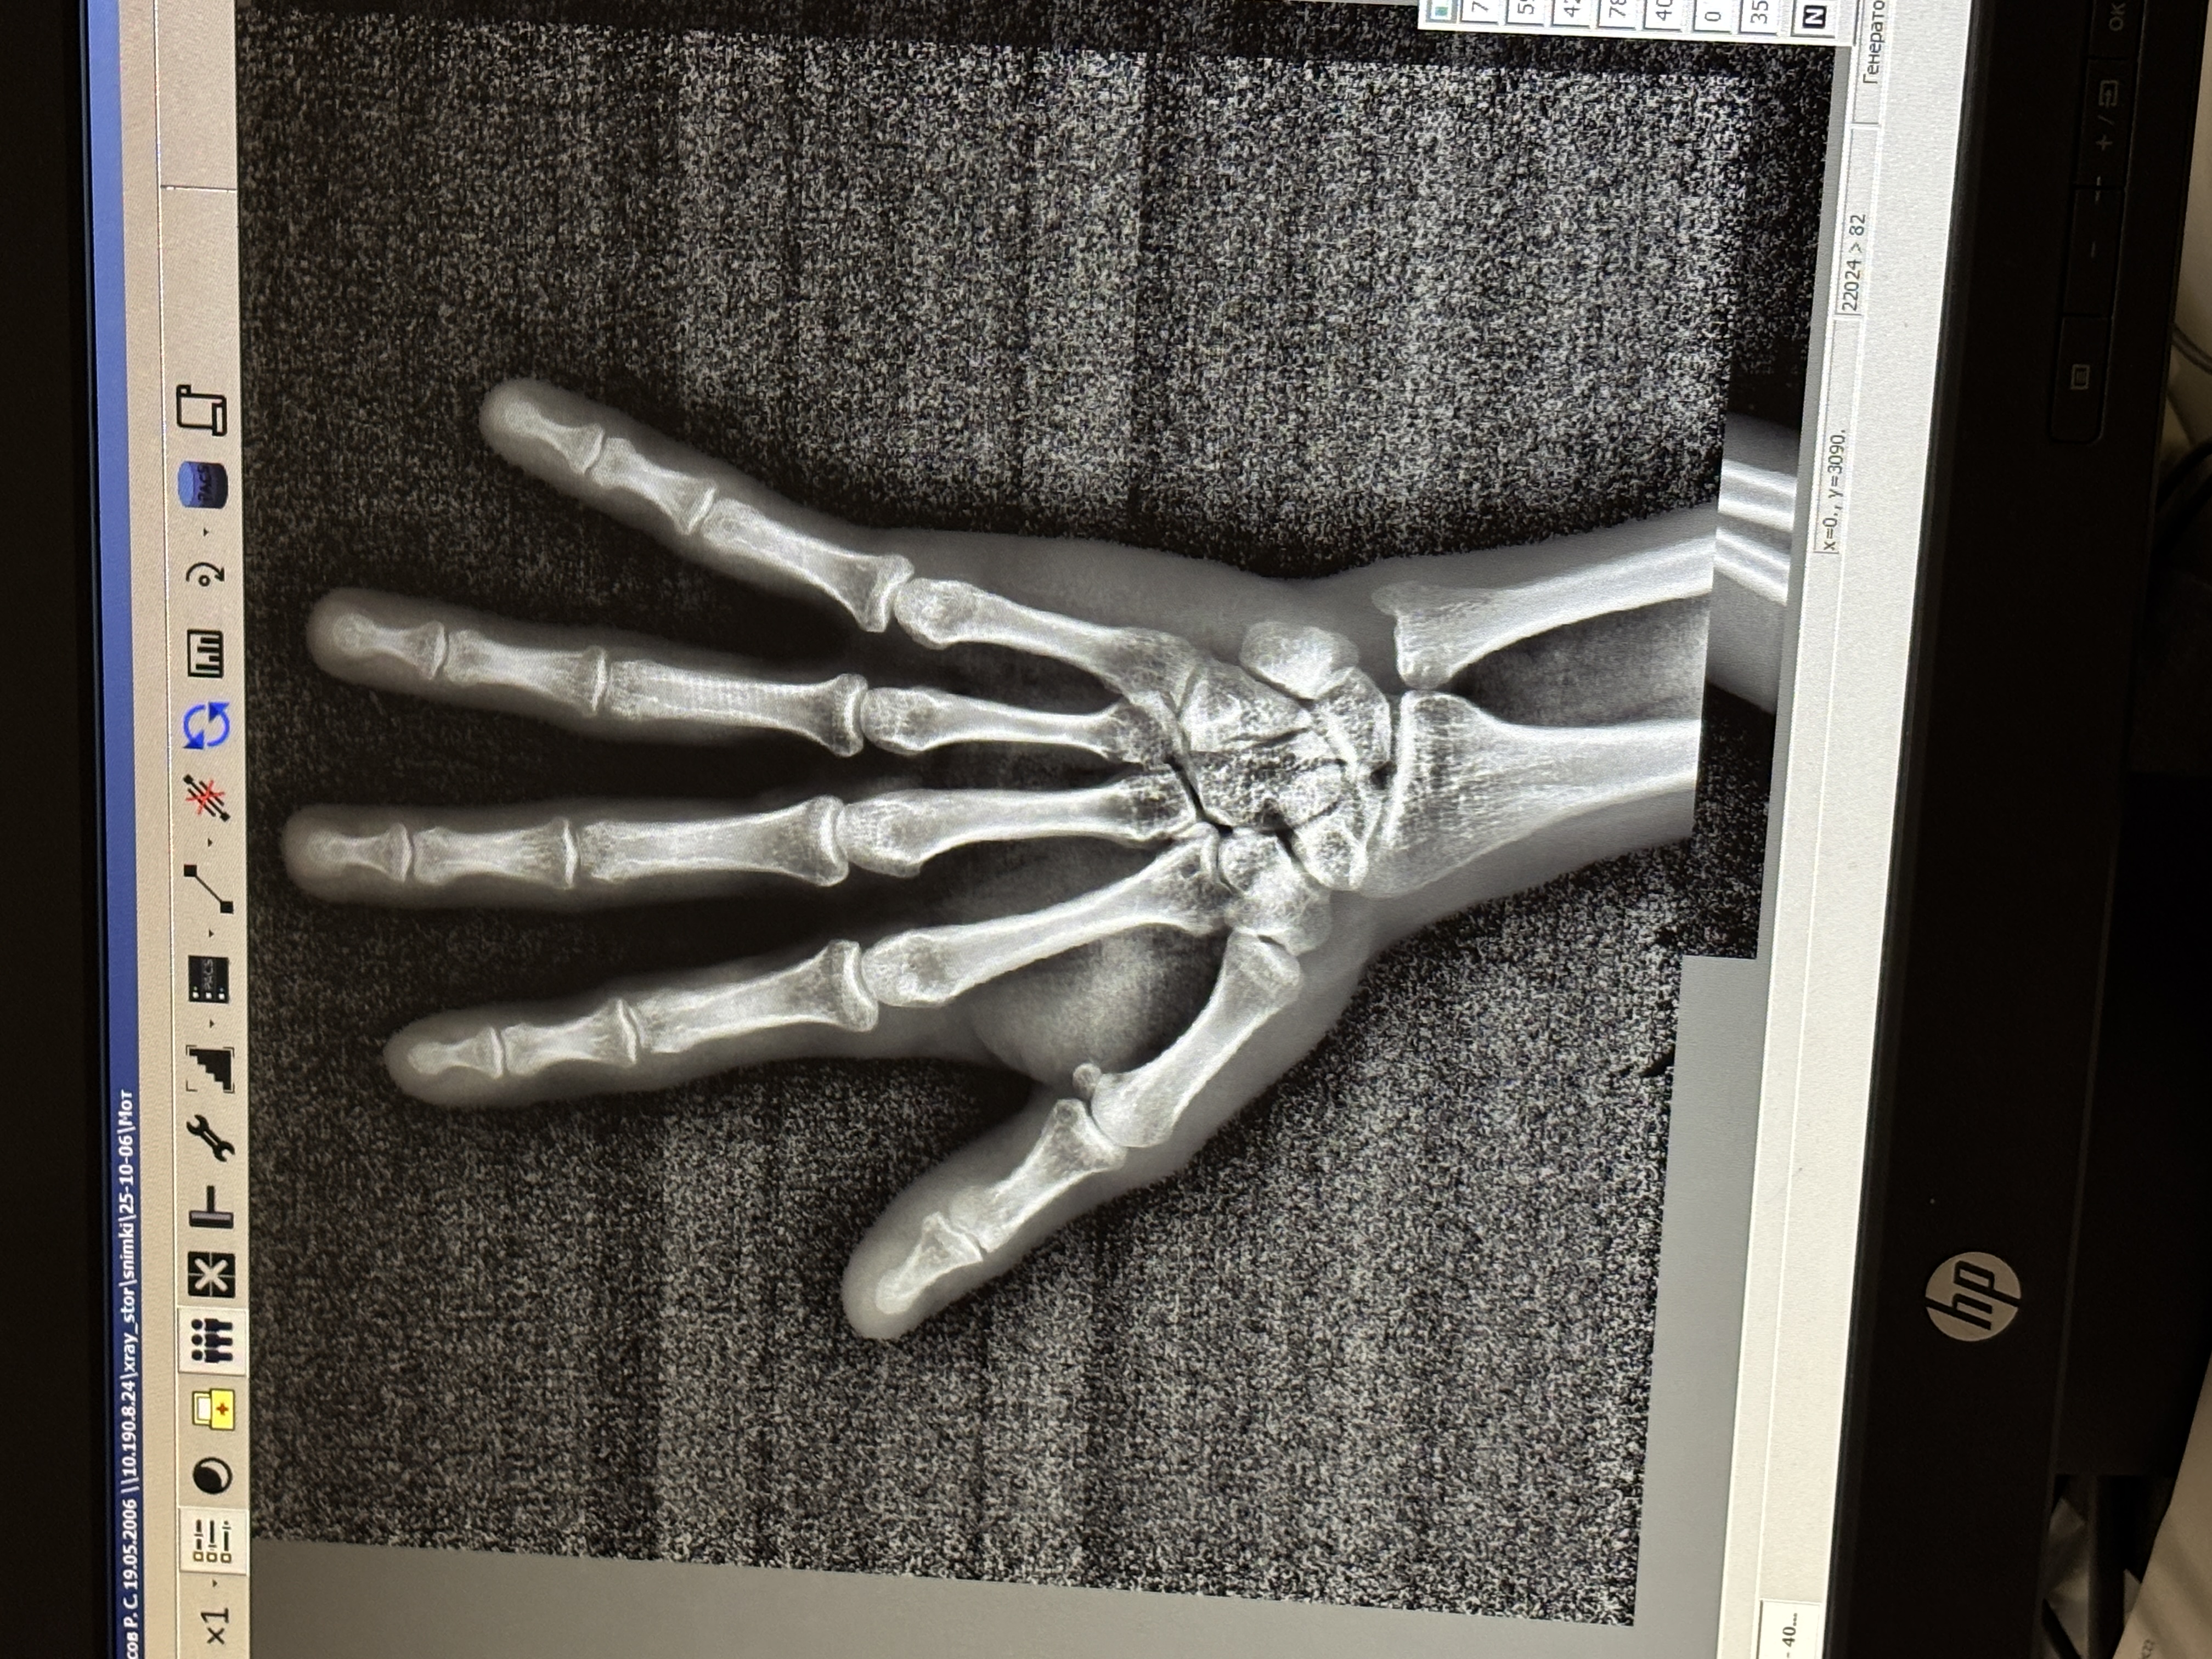

здравствуйте, а у меня закрыты зона раста?

Пол пациента: Мужской пол Тип патологии: Норма, варианты нормы Область исследования: Скелетно-мышечная система Методы исследования: Rg Здравствуйте, мне 17 лет и мой рост утром составляет 178 см, хотел бы узнать, открыты ли еще мои зоны роста. ID:93259 Цель публикации: Консультация Вс, 03/03/2024 - 21:54 #1 NIL Не на сайте Был на сайте: 14 часов 1 минут назад Зарегистрирован: 25.11.2013 - 20:50 Публикации: 18216 В костях предплечья ещё открыты (возрастная норма) "Слушай всех, прислушивайся к немногим, решай сам".© Пнд, 04/03/2024 - 08:18 #2 alisher123 Не на сайте Был на сайте: 2 года 1 неделя назад Зарегистрирован: 03.03.2024 - 20:37 Публикации: 2 Спасибо, но сумею ли я еще вырасти на 5 см и как скоро закроются мои зоны роста? Заранее спасибо. Пнд, 04/03/2024 - 09:25 #3 Андрей Юрьевич Не на сайте Был на сайте: 2 месяцев 4 недели назад Зарегистрирован: 16.11.2008 - 22:16 Публикации: 18101 alisher123 wrote: Спасибо, но сумею ли я еще вырасти на 5 см и как скоро закроются мои зоны роста? Заранее спасибо. - вы слабо представляете работу врачей-рентгенологов, если полагаете, что они отслеживают динамику роста пациентов Андрей Юрьевич Пнд, 04/03/2024 - 18:43 #4 NIL Не на сайте Был на сайте: 14 часов 1 минут назад Зарегистрирован: 25.11.2013 - 20:50 Публикации: 18216 Рост человека прекращается на третьем десятилетии жизни. У мужчин – примерно к 24–25 годам, у женщин – к 20–21 году. Сколько см Вы нарастите в оставшийся срок одному Богу известно. "Слушай всех, прислушивайся к немногим, решай сам".© Пнд, 06/10/2025 - 17:57 #5 rudasaqa Не на сайте Был на сайте: 6 месяцев 2 недели назад Зарегистрирован: 06.10.2025 - 17:51 Публикации: 1 здравствуйте, а у меня закрыты зона раста? Приложения: Пнд, 06/10/2025 - 19:35 #6 NIL Не на сайте Был на сайте: 14 часов 1 минут назад Зарегистрирован: 25.11.2013 - 20:50 Публикации: 18216 rudasaqa wrote: здравствуйте, а у меня закрыты зона раста? Закрыты "Слушай всех, прислушивайся к немногим, решай сам".©

В костях предплечья ещё открыты (возрастная норма)